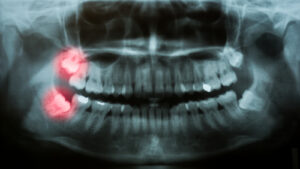

Wisdom teeth are often a topic of concern for many patients, and we get asked…